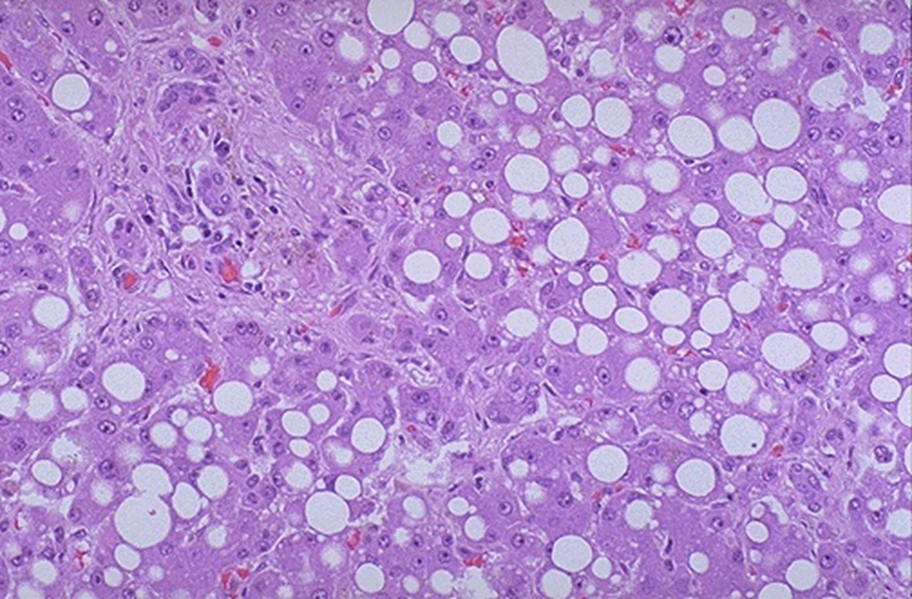

steatosis in alcoholic liver disease

predominantly macrovesicular: fat deposition displaces nucleus

usually reversible, eventual fibrosis around central vein

fatty liver

macrovesicular steatosis in fatty liver